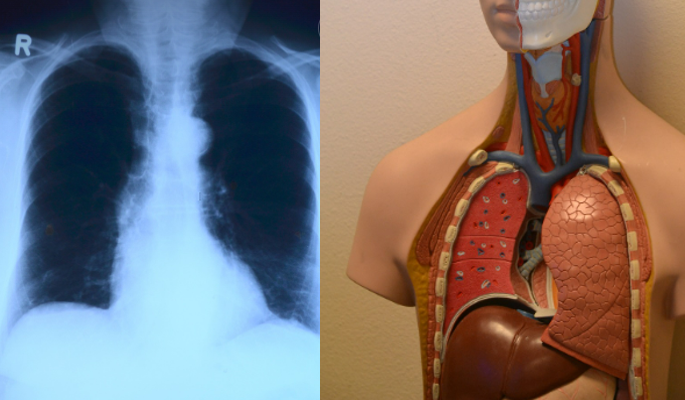

폐암 초기증상 진단 방법과 검사 종류

폐암이 의심될 때 받을 수 있는 검사는 다음과 같습니다:

- 흉부 X-ray: 기초적인 검사이지만 조기 발견률은 낮음

- 저선량 흉부 CT(LDCT): 고위험군 대상 조기 발견을 위한 정밀 촬영으로, 작은 병변도 확인 가능

- PET-CT: 전신 암 전이 여부를 파악하는 데 효과적

- 기관지 내시경: 직접 병변을 보고 조직을 채취해 확진 가능

- 조직 생검: 폐에 주사 바늘을 삽입해 조직을 채취해 암세포 여부 확인

- 혈액 검사(종양표지자): CEA, CYFRA 21-1 등 폐암과 관련된 수치를 확인